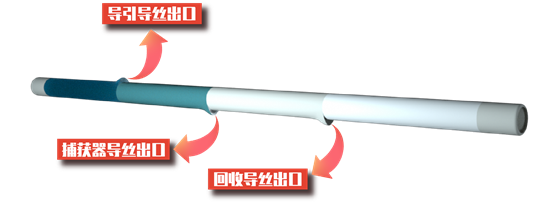

输送鞘管采用分段的硬度设计,远端更软,同时具有出色的抗弯折能力。回收鞘管拥有更大的内腔直径,全段PTFE涂层,摩擦阻力只有同类产品的50%。一体化的输送鞘管和回收鞘管,可与0.014″ 导丝兼容,实现术中快速交换。